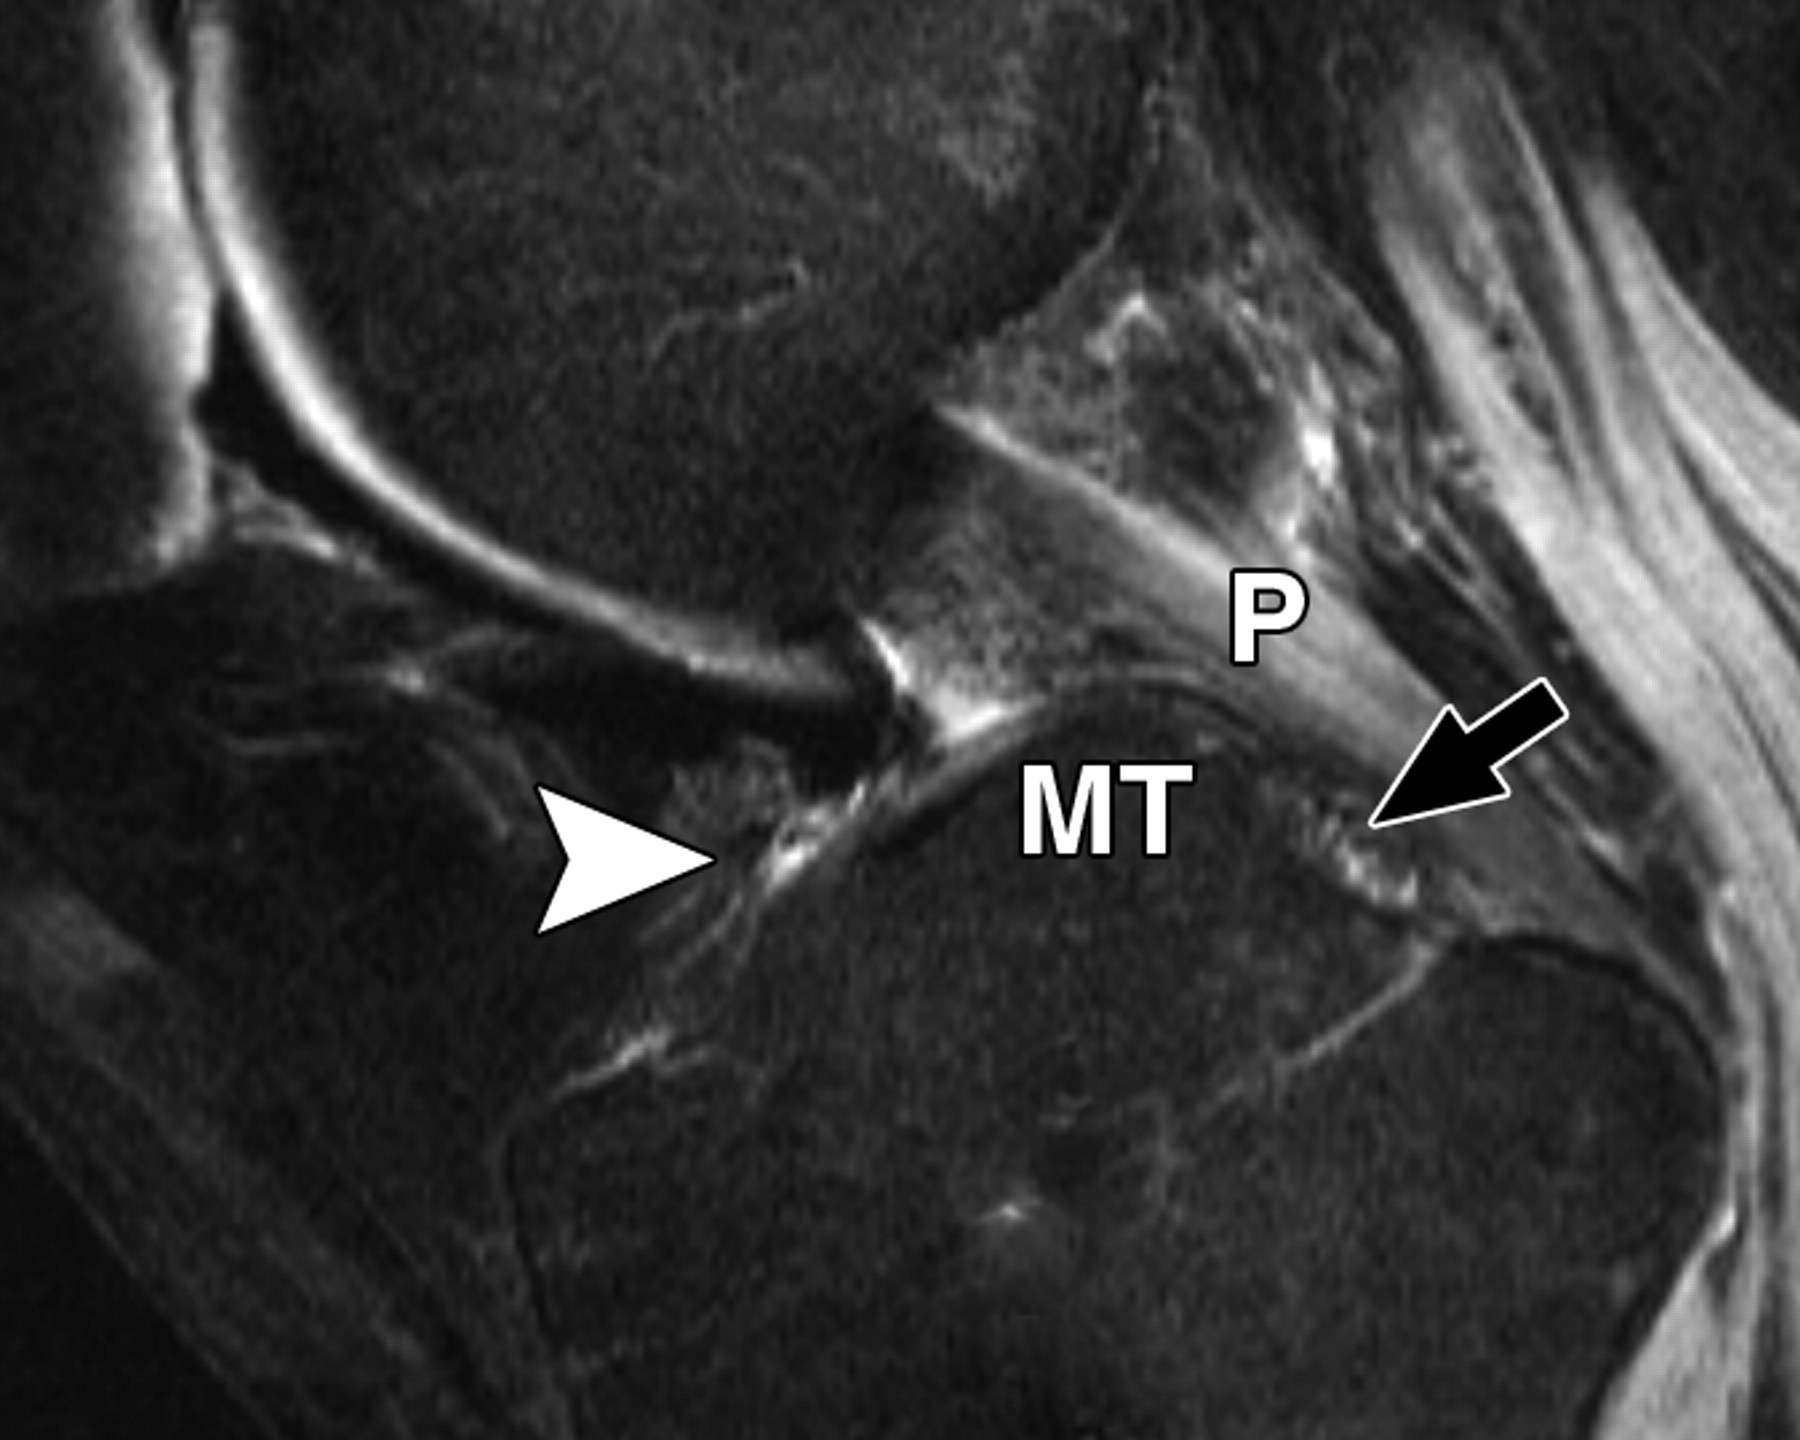

eb13babf5e9b8d8f8cdc165a92bdcb48.jpeg

图3D-51岁女性。

膝关节的中等加权、脂肪饱和、快速自旋回波(TR/TEeff,3,700/29)3-T MR图像显示了膝关节前根、前交叉韧带(ACL)和膝横韧带的解剖关系。B侧位的关节旁MR图像显示外侧半月板前根(箭头)插入处与膝横韧带(白色箭头)后方的ACL(星号)混合。黑色箭头表示里斯伯格韧带。